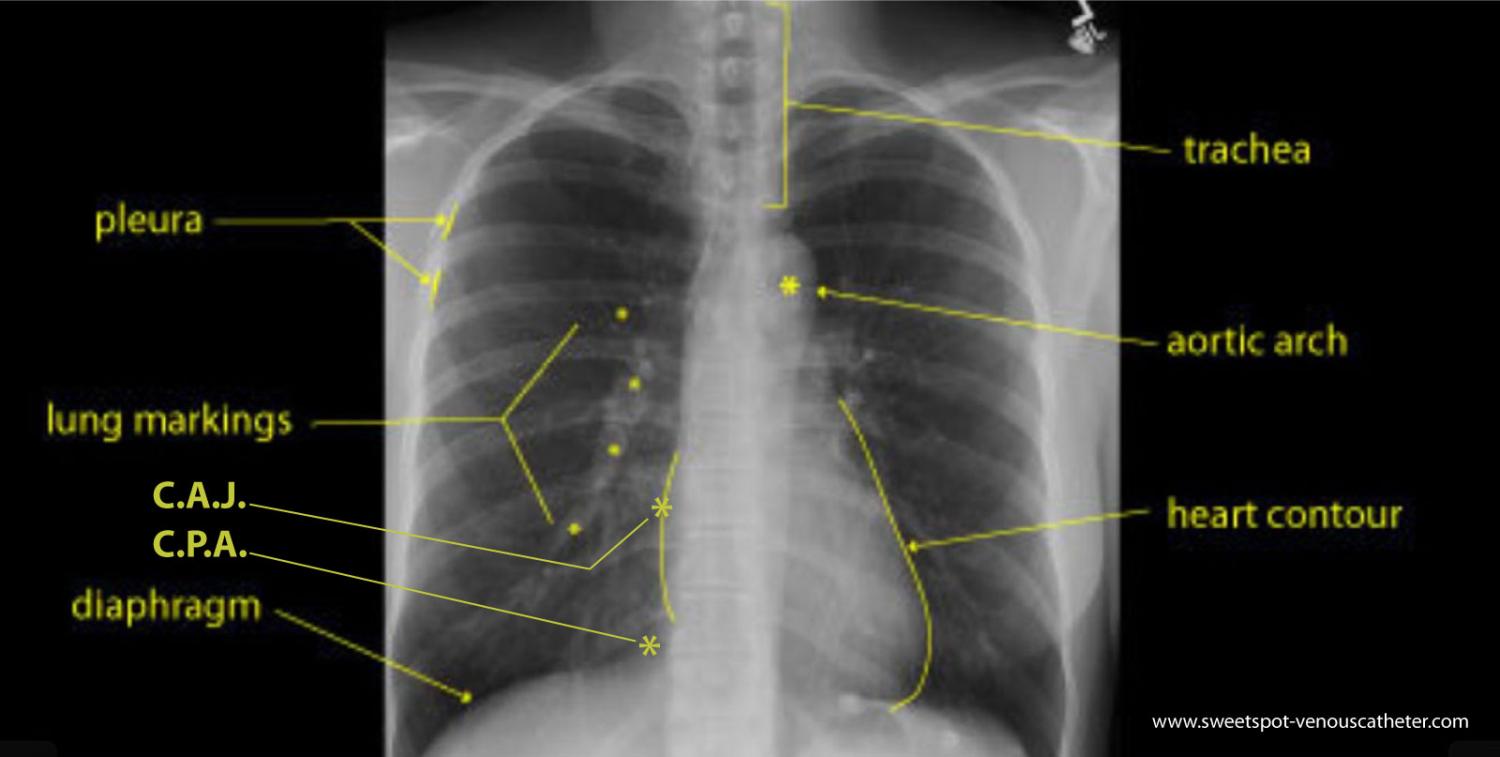

Figure - 19

How to draw the Sweet Spot™ |